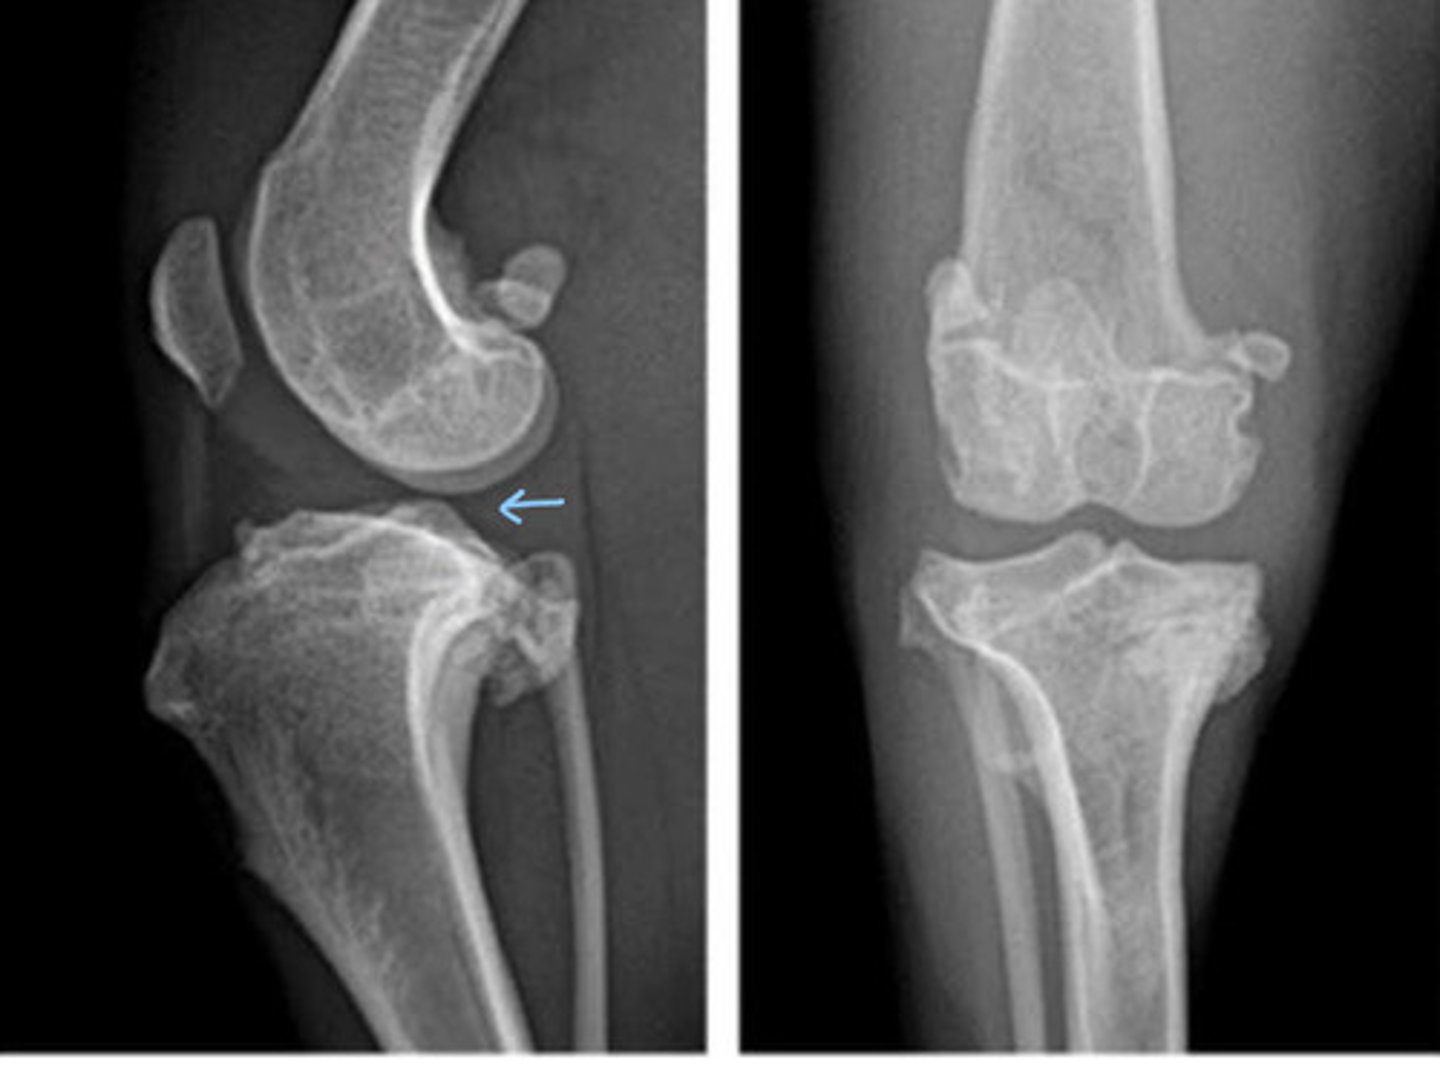

Osteoarthritis

What does this patient have?